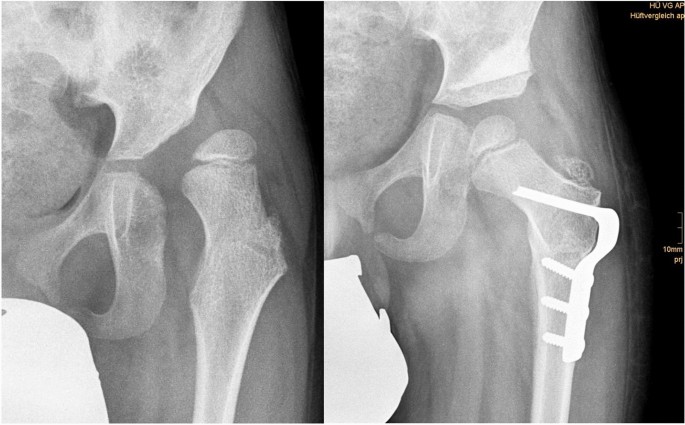

Screening programs for DDH are well established in industrialised countries although the screening technique is not consistently clear [12]. It is commonly accepted that a surveillance program is mandatory to avoid progression of decentration and furthermore dislocation of the hip in children with NDH [13]. Therefore, it is clinical standard to evaluate hips at risk at least annually to prevent painful sub and dislocation. Failed conservative treatment necessarily leads to surgical procedures to reestablish congruency of the joint. Reconstruction of the pelvic joint under usage of pelvic osteotomies in combination with or without derotating varisation osteotomy and soft tissue techniques is a common way to treat DDH and NDH in children (Fig. 2).

Fig. 2

figure 2

Anteriorposterior X-rays of a 6-year-old boy with neurogenic hip dislocation with excellent results 3 months postoperatively